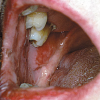

– Üle poolte haigusjuhtudest algab suus esinevate, kiiresti purunevate villidega. Villid on läbipaistvadja pehmed ning piirduvad algul, mõne kuu jooksul, ainult ühe piirkonnaga ja levivad seejärel üle kogu naha. Tervena näiv nahk villi ümber irdub sõrmega vajutades (Nikolsky sümptom).

Suu limaskestal tekivad valulikud erosioonid eelkõige nendes kohtades, mis traumeeruvad toidu

mälumisel ja neelamisel. Tihti on need pemphigus vulgarise puhul esmaseks haiguse väljenduseks. Epiteeli siseselt moodustub kahvatu vill, mis on väga õrn ja peale selle lõhkemist

jääb ebakorrapärase kujuga erosioon. Erosioon on väga pindmine, mistõttu puudub fibrinoosne

katt. Huultel võivad olla koorikud.